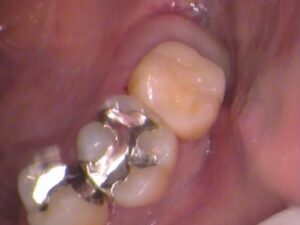

銀歯を削り取って外してみると、

このような状態でした。

接着剤の汚れを取っていくと、

歯の中に白いものが。

セメントといってお薬で以前の治療で詰めてありました。

虫歯が大きく深い箇所に神経を保護するようにセメントが詰められます。

以前の古いセメントも削り取って歯の内部を確認します。